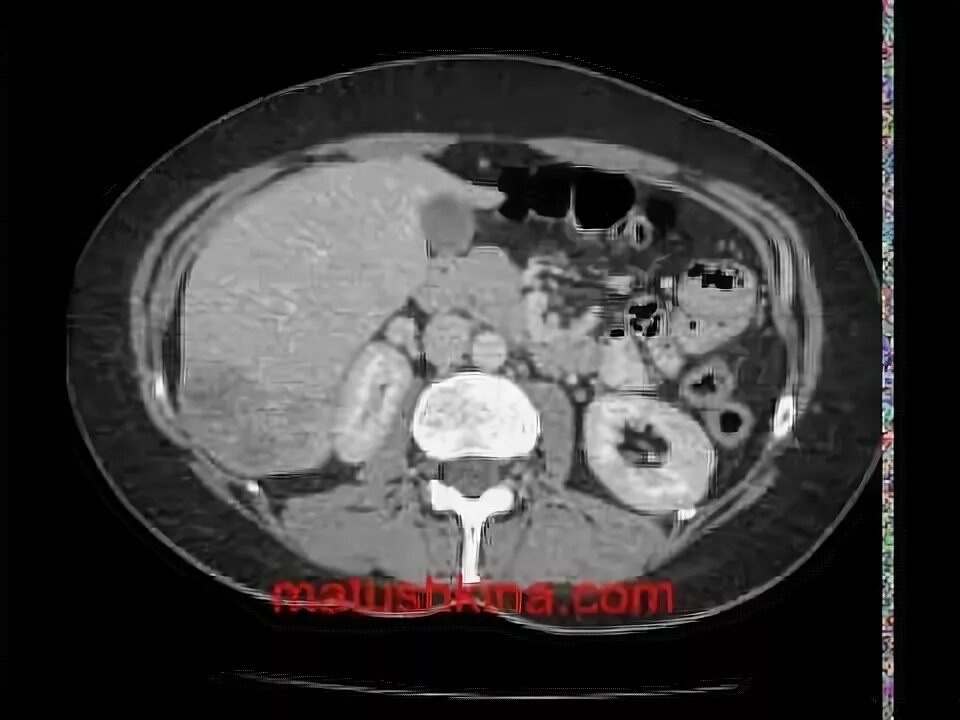

Метастазы после рака кишечника